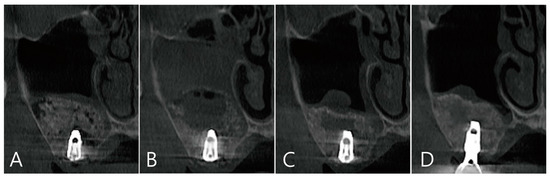

The coronal images of CBCT taken during the healing process after surgery were examined. There was no leakage of bone graft particles in the CBCT taken immediately after surgery (Figure 7A). One week after surgery, a large grafting void was developed over the apical third of the implant, and thickening of the sinus membrane was observed (Figure 7B). The shape of the grafting void after 6 months of surgery became clear and the size decreased. The sinus membrane thickening was also reduced. The void was filled with homogenous contents and showed a cystic appearance (Figure 7C). In the CBCT taken 6 months after the prosthesis was delivered, the bone graft substitute filled the grafting void well (Figure 7D).

Figure 7. Coronal images of the CBCT were taken at multiple points during the healing process after surgery: (A) an image taken immediately after surgery; (B) an image taken one week after surgery. A large grafting void occurred over the apical half of the implant, and thickening of the maxillary sinus mucosa was also observed; (C) in the image 6 months after surgery, the size of the grafting void was slightly reduced. The void presents with a cystic appearance resembling SCC. The apical bony support of the implant was lost. The grafting void was removed and additional bone grafting was performed; (D) in the CBCT image taken 6 months after the prosthesis was delivered, it can be confirmed that the previous grafting void was replaced with a bone graft substitute.